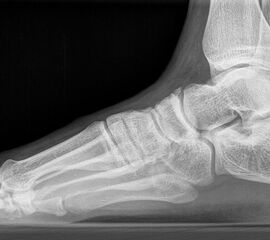

Röntgen

Standard ist die belastete Röntgenaufnahme des Fußes dorso-plantar und seitlich. Günstig ist eine Röhrenkippung von 10°-20°, um die Gelenke der Lisfranc-Linie einsehen zu können.

Ergänzend kann eine Schrägaufnahme hilfreich sein. Bei Metatarsalgien oder Pathologien der Sesambeine liefert die Sprinteraufnahme zusätzliche Informationen. Bei einer Pes planovalgus Fehlstellung wird ergänzend ein Saltzman view durchgeführt.